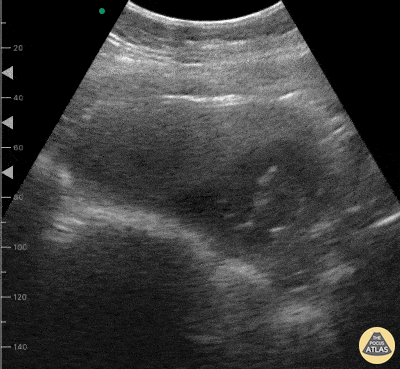

OB/Gyn - Intrauterine Pregnancy

21 year old female presented to the ED reporting lower abdominal discomfort. HPI notable for absent trauma, dysuria, hematuria, constipation, and fever. Last menstrual period was 3 months prior to presentation. POCUS was faster than urine pregnancy test to clinch the diagnosis! Dr. Victor Bang. Emergency Physician at Hospital das Clínicas de Marília. Co-founder of Pocus Jedi. @vmjbang